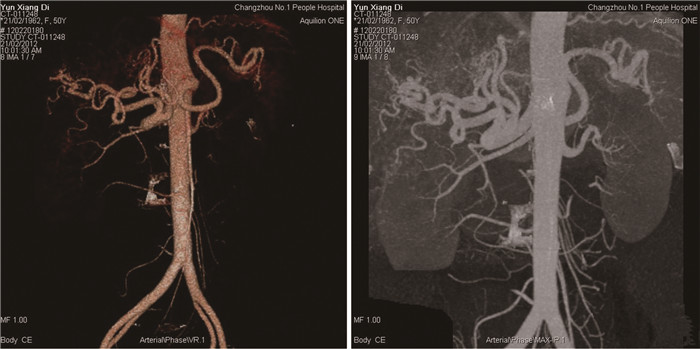

肝脏遗传性出血性毛细血管扩张症1例报告

王婷婷, 马亮, 陈建平

2022, 38(2): 423-425. DOI: 10.3969/j.issn.1001-5256.2022.02.032

摘要(1117) HTML (367) PDF (2696KB)(56)

摘要: